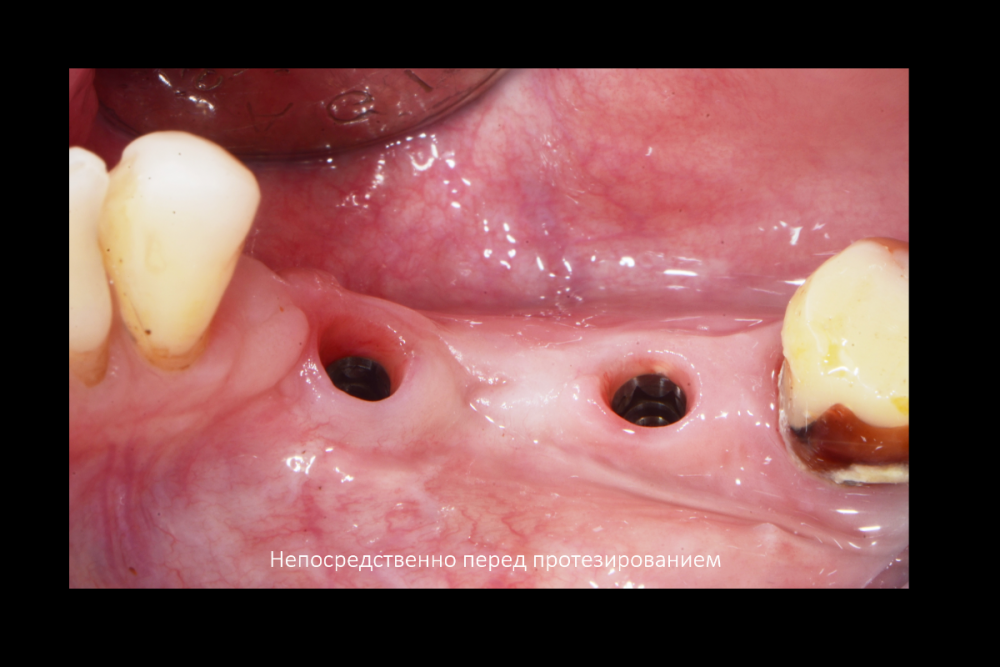

АнтонТЛТ Опубликовано 11 февраля, 2022 Поделиться Опубликовано 11 февраля, 2022 Мембраны под рукой не было? Ссылка на комментарий

Карен Аванесов Опубликовано 11 февраля, 2022 Автор Поделиться Опубликовано 11 февраля, 2022 6 минут назад, АнтонТЛТ сказал: Мембраны под рукой не было? Всегда в запасе. но не в этот раз. Ссылка на комментарий

АнтонТЛТ Опубликовано 12 февраля, 2022 Поделиться Опубликовано 12 февраля, 2022 7 часов назад, Карен Аванесов сказал: Всегда в запасе. но не в этот раз. Я при таких сюрпризах делаю мобилизацию язычного лоскута, вестибулярный не мобилизирую, фдм вторым этапом. Что на 4 слайде справа? Ссылка на комментарий

Irouil Опубликовано 12 февраля, 2022 Поделиться Опубликовано 12 февраля, 2022 Кажется, там какой-то алографт на который сверху подсыпан ксено можно ли проследить вывод из работы, что лучше «без», чем «с»? Ссылка на комментарий

Карен Аванесов Опубликовано 12 февраля, 2022 Автор Поделиться Опубликовано 12 февраля, 2022 15 часов назад, АнтонТЛТ сказал: Я при таких сюрпризах делаю мобилизацию язычного лоскута, вестибулярный не мобилизирую, фдм вторым этапом. Что на 4 слайде справа? Делал и так ка ты написал. коллаген 15 часов назад, Irouil сказал: Кажется, там какой-то алографт на который сверху подсыпан ксено можно ли проследить вывод из работы, что лучше «без», чем «с»? Именно! и не только. Полезно смотреть старые работы. только не все пациенты исправно приходят Ссылка на комментарий

Bier Опубликовано 14 февраля, 2022 Поделиться Опубликовано 14 февраля, 2022 от подобной присыпки толку обычно нет. Ссылка на комментарий

Карен Аванесов Опубликовано 15 февраля, 2022 Автор Поделиться Опубликовано 15 февраля, 2022 13.02.2022 в 22:56, Fin сказал: Карен. Подскажите пожалуйста. Правильно ли я понял, что в на данный момент в такой ситуации (оголение импланта с вестибулярной стороны на половину) Вы бы обошлись просто установкой импланта + ССТ вестибулярно? Да, именно так. 14.02.2022 в 10:33, Bier сказал: от подобной присыпки толку обычно нет. Олег, помнишь аник "темно здесь..." Вот только не начинай про полужесткие сосиски)))) Но ты прав или делпать по отработанной технологии или никак 1 Ссылка на комментарий